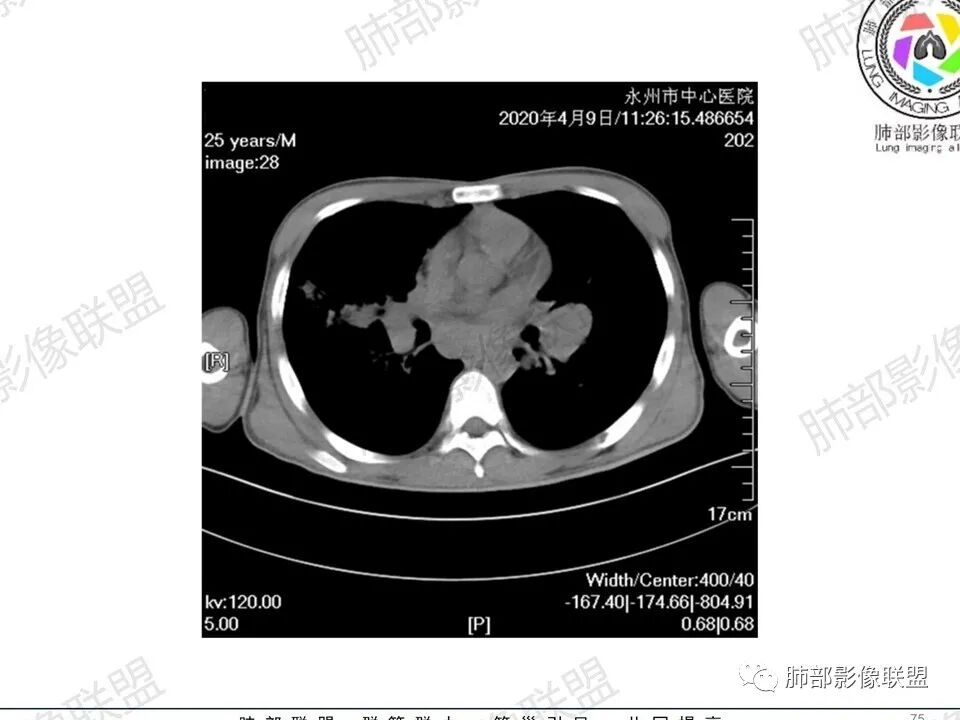

3、影像表现:双肺散在斑片影及结节影,部分结节内可见血管穿行,斑片影沿支气管血管束分布,近胸膜侧病变收缩不明显。部分中央淋巴间质增厚,小叶间隔增厚。病灶内支气管穿行,部分支气管略扩张。局部小结节呈串珠样改变。纵隔、肺门区、锁骨上及腋窝淋淋巴结肿大,部分有融合。心腔低密度。脾大。

5.双肺门及纵隔淋巴结显著增大,这改变相当显眼。这里强调“双肺门”及“多发”!

增大的淋巴结密度偏低且均匀。此外患者有体表淋巴结增大。

1.临床表现明显,纵隔及双肺门淋巴结显著肿大,临床最为担心的还是淋巴瘤!

尤其患者有贫血及脾脏增大,又有体表淋巴结增大时,这也是临床相对常见的情形。